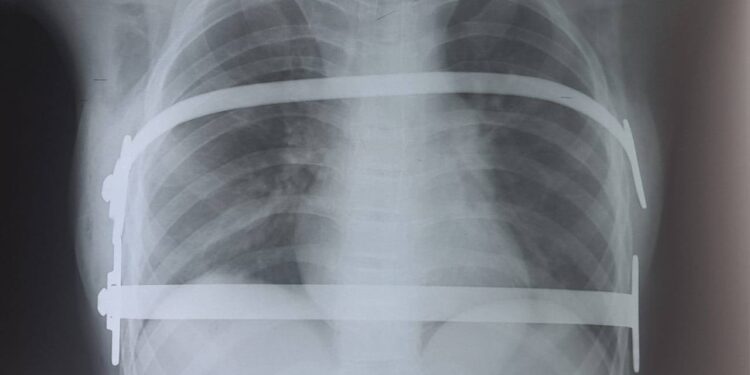

Бригадою дитячих лікарів КНП “Миколаївська обласна дитяча клінічна лікарня” МОР під головуванням доктора філософії Віталія Заремби вперше в регіоні виконано модифіковане відеотороскопічне втручання Nuss із паралельною імплантацією двох титанових пластин 12-річній дитині з діагнозом «Вроджена лійкоподібна деформація грудної клітки, асиметрична, незбалансована».

На даний час прооперована дитина виписана додому, почуває себе задовільно та готується до проходження реабілітації в умовах філії «Центр медичної реабілітації та паліативної допомоги».